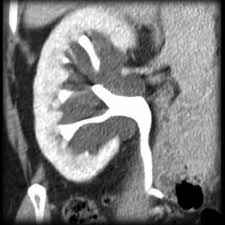

Renal cysts are usually circular filled with clear fluid and have no connection to the pyelocalyceal system. This can be due to disease processes such as polycystic kidney disease although no cause for the formation of these cysts is found in some patients. Kidney cysts are round fluid filled sacs that form in the kidneys.

Renal cysts become bilateral when they are present in both kidneys.

Renal cysts become bilateral when they are present in both kidneys. One or more may form within the kidneys simple cysts are the most common. Also known as percutaneous alcohol ablation sclerotherapy involves the insertion of a long needle through the skin and into the cyst under ultrasound guidance. If there are a number of them in both kidneys they become known as multiple bilateral cysts.